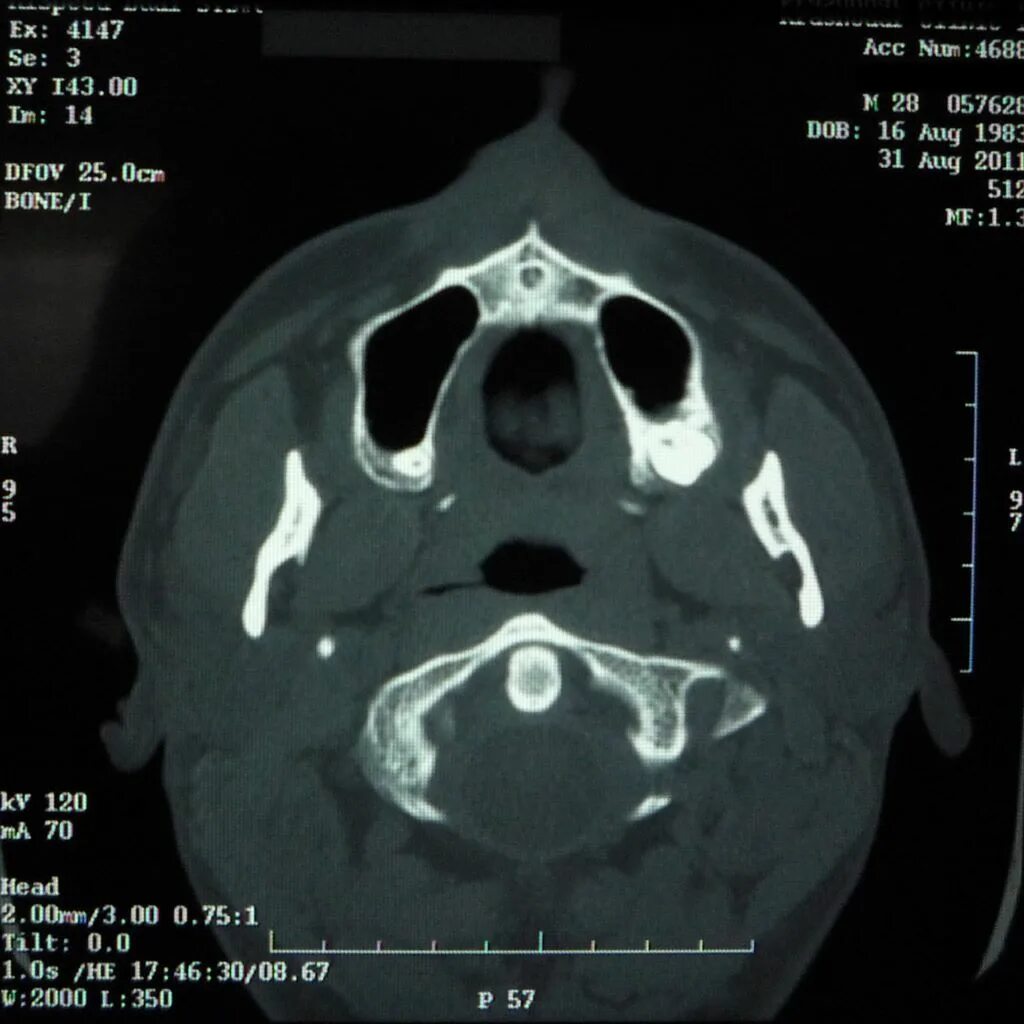

Череп на кт